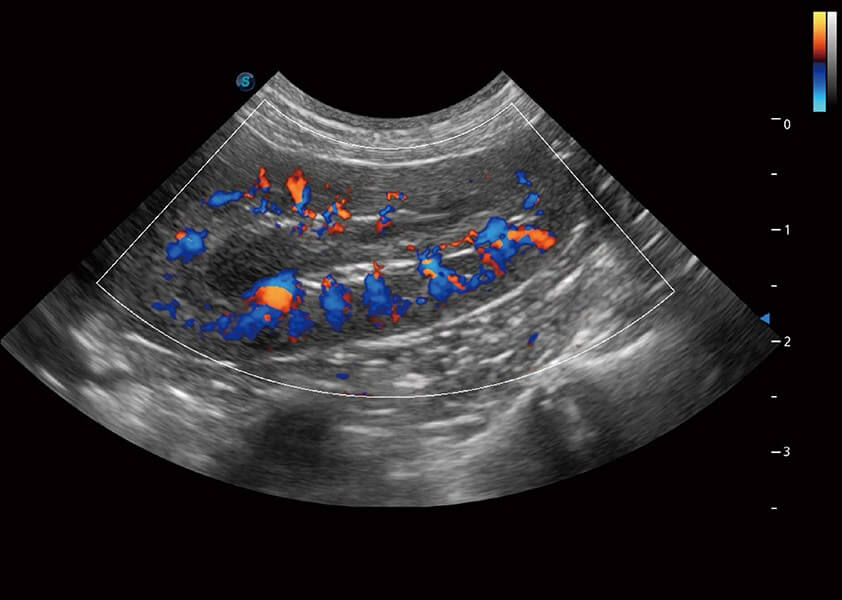

4T血流成像 微察秋毫

融合不同血流成像技术的优势,即可以提升血流成束性,同时可提高血流的视觉敏感性。

Micro F 显微血流成像

通过创新的Matrix E自适应滤波器和超长时间域算法,极大提升超低速微细血流的检出能力,同时更精准地滤除软组织和噪声信号,为兽用医生提供以往无法通过常规血流获得的疾病诊断信息。

Bright Flow 立体血流成像

在传统二维血流成像的基础上,呈现血流的立体感,具有动感的生命力之美。精确区分不同血管的空间关系,提高了血流的视觉敏感性。

(犬)肾脏血流